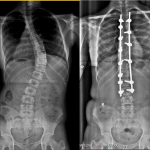

Idiopathic Scoliosis

IDIOPATHIC SCOLIOSIS Rishi Mugesh Kanna, MS, MRCS, FNB(spine), Spine Surgeon, Ganga Hospital, Coimbatore, India Introduction Scoliosis refers to lateral curvature of the spinal column of more than 10 degrees when observed through an antero-posterior radiograph of the spine. There are different causes of scoliosis and the causes vary depending on the age of onset. In […]